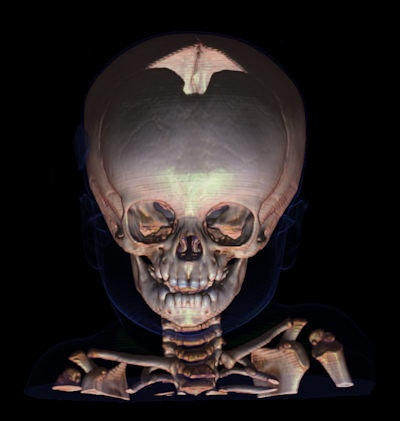

Session chairman Dr. Fabrice Dedouit, from the Centre Hospitalier Universitaire de Toulouse, and Mangin provided an overview of the state-of-the-art technology for this developing field, demonstrating the benefits of a nondestructive examination in contrast to traditional autopsies. Virtual autopsies using CT offer a credible alternative in cases in which there are religious or cultural objections to surgical autopsy, and in cases in which it may be unsafe to open a body, such as with victims of a suspected bioterrorist attack. There is also critical evidence regarding causes of death and methods of death that can be determined with a visual study of embolic gases that are lost once the body is opened.

"Give me your bones and I'll tell you who you are," said Dedouit, who showed how CT can be used to identify corpses destroyed beyond recognition in crashes, or skeletons found in the woods, thanks to anatomical signatures, such as prostheses that match radiological records and even jewelry fused to the body. Half of all identification matches are made with radiographic records of the thorax, and a quarter is based on variations in anatomy.